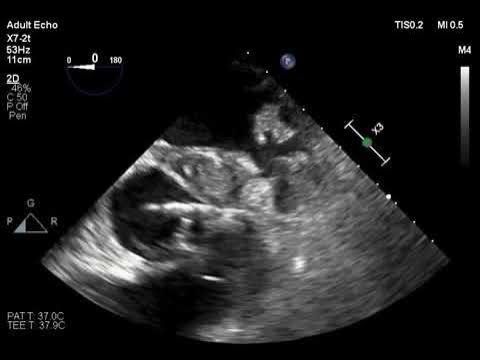

Narrowing of Coronary Arteries and Presence of Aortic Root Abscess

Perivalvular Abscess Causing Coronary-Artery Compression An afebrile 67-year-old woman presented to the emergency department with fatigue and anorexia. Three ...

Source: https://youtu.be/qNud6KL0oMw?si=mmjYyw7oAahgBPkN